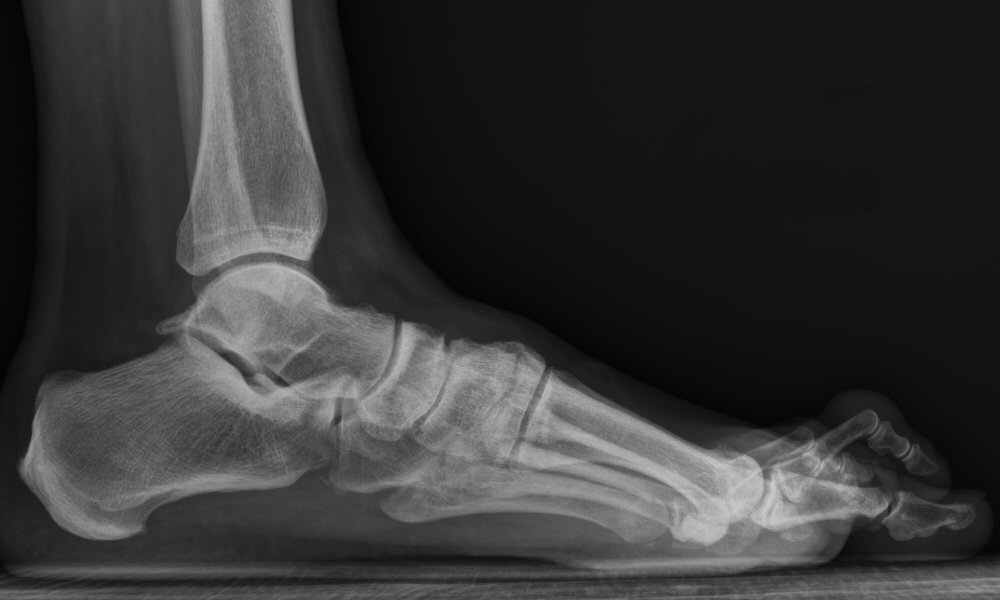

Röntgenbild resp. foto, hammartå dig 2

Kontrollera att man provat icke-kirurgisk behandling och att det finns aktuella belastade röntgenbilder av foten (röntgen i stående).